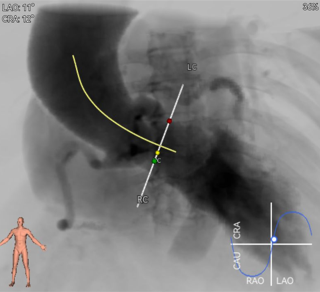

罗建方教授 广东省人民医院(点击查看专家详细简历) 设计本为临床需,耐久守护好芳华:任何医疗产品的设计初衷与最终归宿,都应落在 “临床获益” 这一核心上。尤其在 TAVR 领域,年轻患者预期寿命长,术后瓣膜的长期性能直接关乎其生活质量与生存预后。瓣膜耐久性问题,是落到临床实践中亟待突破的关键课题。传统瓣膜在长期使用中,可能因结构老化、功能退化等问题,难以满足年轻群体数十年的健康需求,二次手术风险也随之攀升。因此,产品设计必须直面这一临床痛点:通过材料革新增强抗钙化性能及生物相容性,以技术突破延长瓣膜有效使用寿命。此次临床应用的预装干瓣Prostyle A®是TAVR领域的革新理念,干瓣预期会为临床提供更耐久性的保障,实现了与临床需求的精准对接,为年轻群体的瓣膜治疗提供更坚实的保障。 李捷教授 广东省人民医院(点击查看专家详细简历) 干瓣技术求革新,性能兼顾护临床:干瓣的技术革新在创新的同时需要和临床实际需求深度耦合,兼顾TAVR术中的核心考量点。临床操作中,瓣膜能否顺利过弓,直接影响手术效率与安全性。Prostyle A®短瓣架设计及第二台阶的柔顺设计,术中操作丝滑;同时,瓣膜植入后的径向支撑力必须平衡得当,才能实现稳定锚定;释放后造影显示:瓣膜形态舒展,轻度瓣周漏,舒张压升高,冠脉开口未受影响;瓣周漏是影响术后效果的关键隐患,双层裙边设计通过多重密封机制降低反流风险,为患者长期获益筑牢防线。这些性能的协同优化,最终目的是让干瓣在临床中真正做到 “好用、耐用、安全用”,为患者预后提升提供坚实支撑。 患者病史 患者因 “活动后气促伴头晕 2 月” 入院。 现病史:2月前无诱因出现活动后气促,休息后缓解,伴头晕,夜间阵发性呼吸困难。超声检查发现:主动脉瓣重度狭窄并重度返流(跨瓣流速 4.3m/s,峰值压差 73mmHg);主动脉 + 冠状动脉 CTA 提示主动脉瓣显著钙化,升主动脉及分支粥样硬化,冠状动脉轻度狭窄(RCA 狭窄 30-40%)。 既往史:高血压病史 15 年,规律服药,血压控制稳定。 术前诊断:非风湿性主动脉瓣狭窄伴关闭不全(重度)、心功能 II 级(NYHA)、高血压病 2 级(高危)、冠状动脉粥样硬化。 术前CT 三叶瓣,瓣叶增厚中度钙化,右无交界钙化粘连,瓣环径25.1mm,LVOT 25.1mm,直筒型结构;窦部空间足够,升主未见增宽,瓣环水平夹角55°;冠脉开口位置佳,无冠脉风险;入路散在钙化、外周双侧入路无明显迂曲,双侧内径可、中分叉,左右侧均能够支持20F 大鞘通过。 造影角度及入路 右窦居中位RAO 5° CAU 26° 左冠切线位LAO 11° CRA 12° 手术策略 右侧股动脉为主入路,左侧为辅助入路;使用20球囊预扩,准备AV26瓣膜,冲洗口朝向3点钟方向送入输送系统性能,初始定位真实瓣环0位释放,最终锚定约瓣下3mm,工作位评估瓣膜稳定性与冠脉情况。 手术过程 根部造影 20mm 球囊预扩无明显腰征 术中使用26号瓣膜,瓣膜释放贴边迅速 80% 工作位观察瓣膜位置良好 释放后造影显示:瓣膜形态舒展,轻度瓣周漏,舒张压由术前30mmHg升为 60mmHg,冠脉开口未受影响。 术后超声:跨瓣流速降至1.6m/s,平均压差降至5 mmHg,心功能显著改善。 Prostyle A®预装干瓣——助力临床最优化解决方案: 1. 抗钙化与耐久性:Micro-EX™专利技术提升瓣膜抗钙化能力,适配患者瓣叶中度钙化的解剖特点,为长期疗效提供保障。 2. 柔顺过弓与精准定位:短瓣架设计 + 远端超滑涂层,确保患者输送系统过弓顺畅;瓣架流入端微直筒设计,让定位贴边更迅速,减少了手术时间; 3. 80% 可回收设计:便于术中调整观察,减少起搏时间,从而减少并发症。 4. 简化手术流程:预装设计缩短操作时间,20F 大鞘兼容外周入路,降低血管损伤风险。